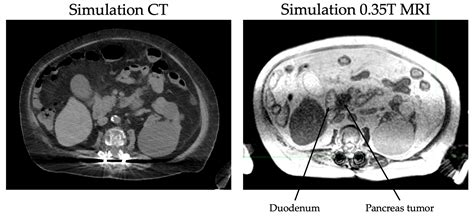

CT scans can detect pancreatic cancer by identifying masses or tumors within the pancreas. These tumors may appear as areas of increased density or irregular shapes. Additionally, CT scans can assess the extent of disease spread, helping healthcare providers determine the appropriate treatment plan.

In some cases, CT scans may be used in conjunction with other imaging techniques, such as Magnetic Resonance Imaging (MRI) or Positron Emission Tomography (PET) scans, to provide a more comprehensive assessment of the disease.